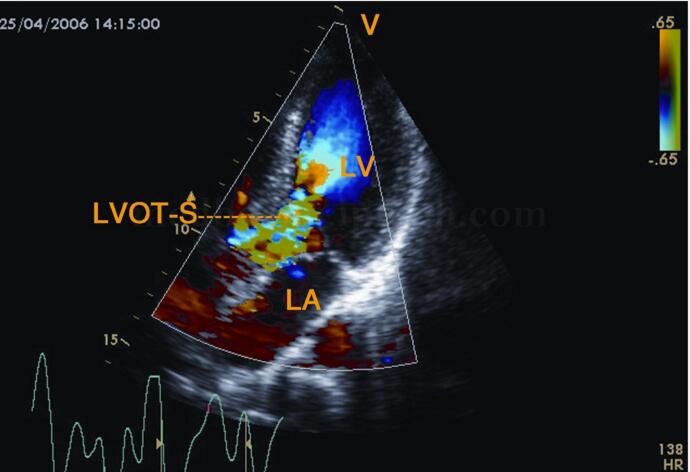

3﹒彩色多普勒超声

(1)左室流出道梗阻者:收缩早期左室流出道内充满五彩细窄血流束,向主动脉瓣及瓣上延伸,狭窄越重,色彩混叠越严重。彩色血流最窄的部位即为左室流出道梗阻部位(图2‐1‐207)。

图2‐1‐207 左室流出道梗阻者,收缩早期流出道内见五色镶嵌细窄射流束